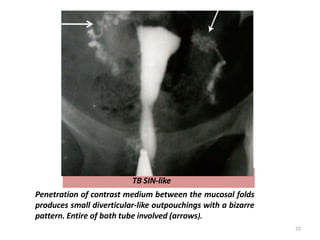

TB SIN-like

Penetration of contrast medium between the mucosal folds

produces small diverticular-like outpouchings with a bizarre

pattern. Entire of both tube involved (arrows).